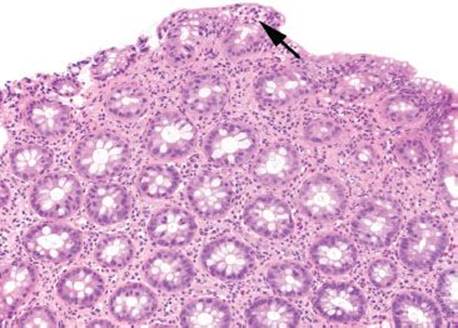

Figure 4.19 Focal active colitis pattern. This low magnification emphasizes the orderly architecture of the colonic crypts. Cut in cross section, they appear like an evenly spaced bed of flowers. A single isolated focus of acute inflammation (arrow) is present at the surface.

Figure 4.20 Focal active colitis pattern. Higher magnification of the previous case shows an isolated focus of acute inflammation (arrow) in a background of unremarkable colonic mucosa.